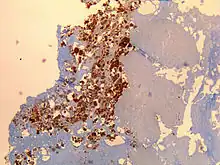

Signes histologiques

Ponction biopsie hépatique : permet de découvrir des granulomes en beignets avec un anneau de fibrine[7].